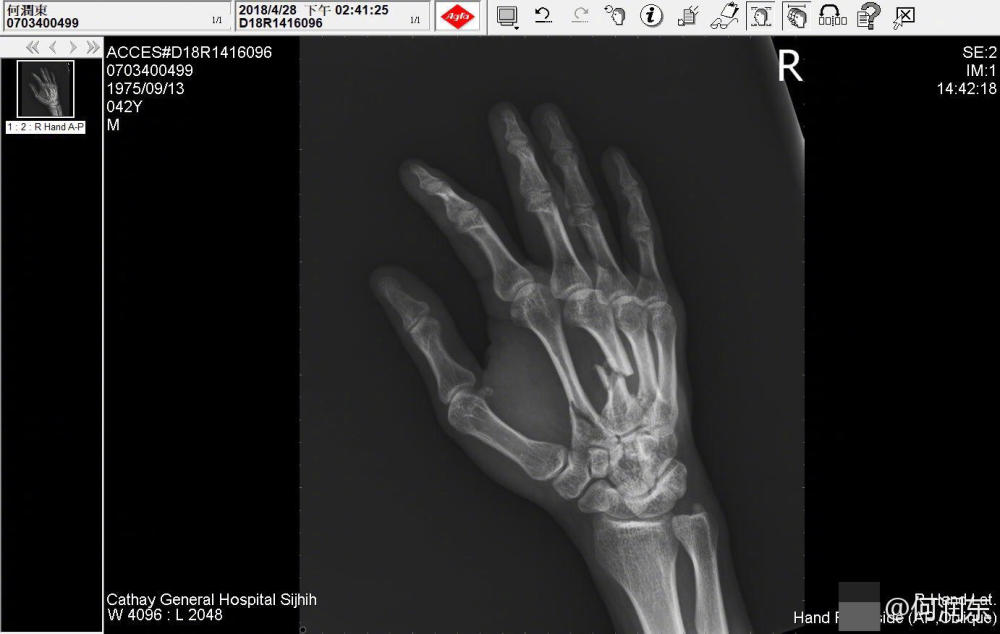

手部x光

手部x光,手部核磁共振

手部正反面x光图像

不同角度手部x光图像

这是固定钢钉后的x光片,不知这样对于酷爱运动的何润东而言,手部

右手x光片

正常手骨x光图右手

正常右手x光片